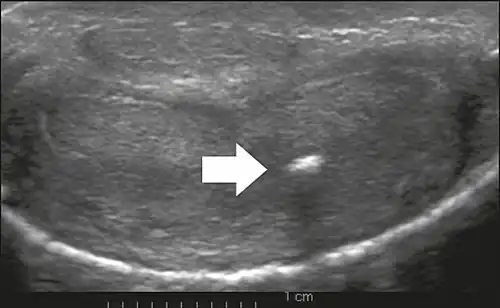

This ultrasound depicts cross sections of the penis at different locations in a patient with Peyronie's disease. The top image shows normal anatomy whereas the bottom image shows scar tissue on the tunica albuginea (penis). The scar tissue is localized and responsible for the hallmark deformities of Peyronie's disease (curvature and narrowing).

Ultrasonography

On penile ultrasonography, the typical appearance is hyperechoic focal thickening of the tunica albuginea. Due to associated calcifications, the imaging of patients with Peyronie's disease shows acoustic shadowing, as illustrated in figures below. Less common findings, attributed to earlier stages of the disease (still mild fibrosis), are hypoechoic lesions with focal thickening of the paracavernous tissues, echoic focal thickening of the tunica without posterior acoustic shadowing, retractile isoechoic lesions with posterior attenuation of the beam, and focal loss of the continuity of the tunica albuginea.

In the Doppler study, increased flow around the plaques can suggest inflammatory activity and the absence of flow can suggest disease stability. Ultrasound is useful for the identification of lesions and to determine their relationship with the neurovascular bundle. Individuals with Peyronie's disease can present with erectile dysfunction, often related to venous leakage, due to insufficient drainage at the site of the plaque. Although plaques are more common on the dorsum of the penis, they can also be seen on the ventral face, lateral face, or septum.[14]